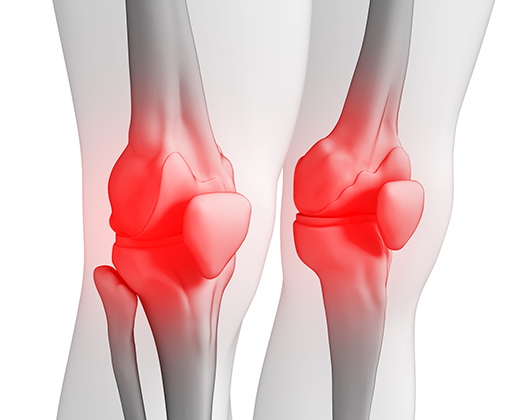

무릎의 연골도 대부분 관절과 동일하게 뼈를 매끄럽고 마찰이 덜가게 생성해 주는 미끄러운 연골 층으로 둘러 축적되어 있어요. 뿐 아니라, 무릎 중앙에는 부가적인 충격 흡수를 전달하는 반월상 연골이라고 하는 두 개의 고무질 반원형 연골 조각이 있어요.

무릎 연골 증상 아니면 무릎 연골 찢어짐은 전문적인 말로 무릎 반월상 연골판 파열이라고요. 반월상 연골은 우리가 무릎을 이용하는 즉 걷거나 뛰거나 점프한 경우 혹은 등때문에 충격을 흡수시켜주는 역할을 해요.

다른 관절과는 차이나게 충격을 잘 흡수해주기 위해 탄력성을 가진 섬유 연골 구조로 되어있어요. 우리가 평상시 과도한 운동을 한 경우 혹은 무릎을 풍부하게 쓰는 행동을 한다면 무릎관절에 3배의 힘이 전해진다고 해요. 그리고 외부로부터 충격을 섭취한다던지 큰 힘을 쓰게 될 경우 무릎 연골 찢어짐때문에 통증이 유발되게 되는 거에요.